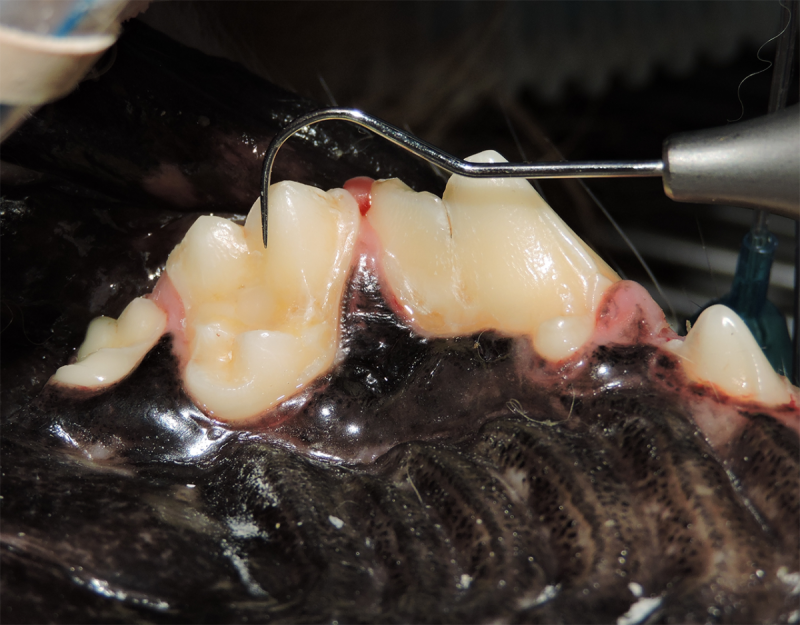

Tooth resorption is a disease process where the body begins to break down the adult tooth. It is widely known to occur in cats but can also occur in dogs. In cats these lesions are thought to be inflammatory, while in dogs they can be more of a replacement resorption process. These lesions can be very painful and should be treated, generally with extraction depending on the type of resorption that is occurring. The disease can be progressive and affect many teeth over several years. It is important to have regular checkups and yearly dental cleanings to monitor for these lesions.